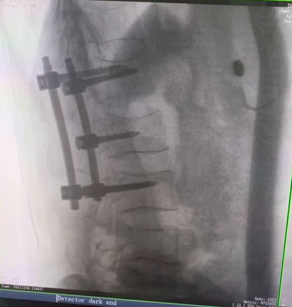

例如治療先天性脊柱側(cè)后凸畸形,由于脊柱自身復(fù)雜的解剖結(jié)構(gòu)限制,使得脊柱外科手術(shù)對(duì)于精確度有著較高要求。以往我們只能采用傳統(tǒng)的正側(cè)位圖像來判斷螺釘置入的位置,現(xiàn)在三維C形臂特有的類CT斷層成像,使得治療過程可視化,立體化,在術(shù)中非常直觀地判斷螺釘植入的準(zhǔn)確度。可有效引導(dǎo)術(shù)者植入后路螺釘并切除半錐體。同時(shí)可以在術(shù)中實(shí)時(shí)驗(yàn)證手術(shù)效果。有效地縮短了手術(shù)時(shí)間,降低手術(shù)風(fēng)險(xiǎn),避免了不必要的術(shù)后翻修手術(shù)。

另外,三維C形臂采用12英寸(30cm x 30cm)的平板探測(cè)器,成像區(qū)域大,有效成像面積比9英寸傳統(tǒng)影增提升了100%,可一次拍七節(jié)頸椎、五節(jié)腰椎、十二節(jié)胸椎、雙側(cè)骶髂關(guān)節(jié)、股骨頭及單側(cè)盆骨。